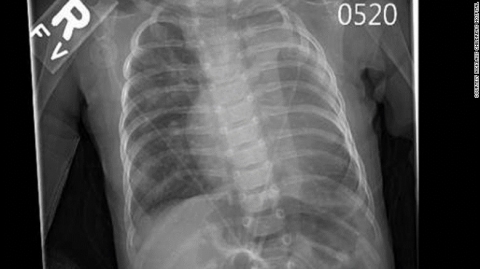

少了一個肺和一半的心臟

小迪根去年8月時才出生,她的心臟和肺都存在缺陷,醫(yī)生之前還沒見過這樣的病例。她只有一個肺,幾乎沒有左心室。

迪根出生時只有一個肺的一半的心臟